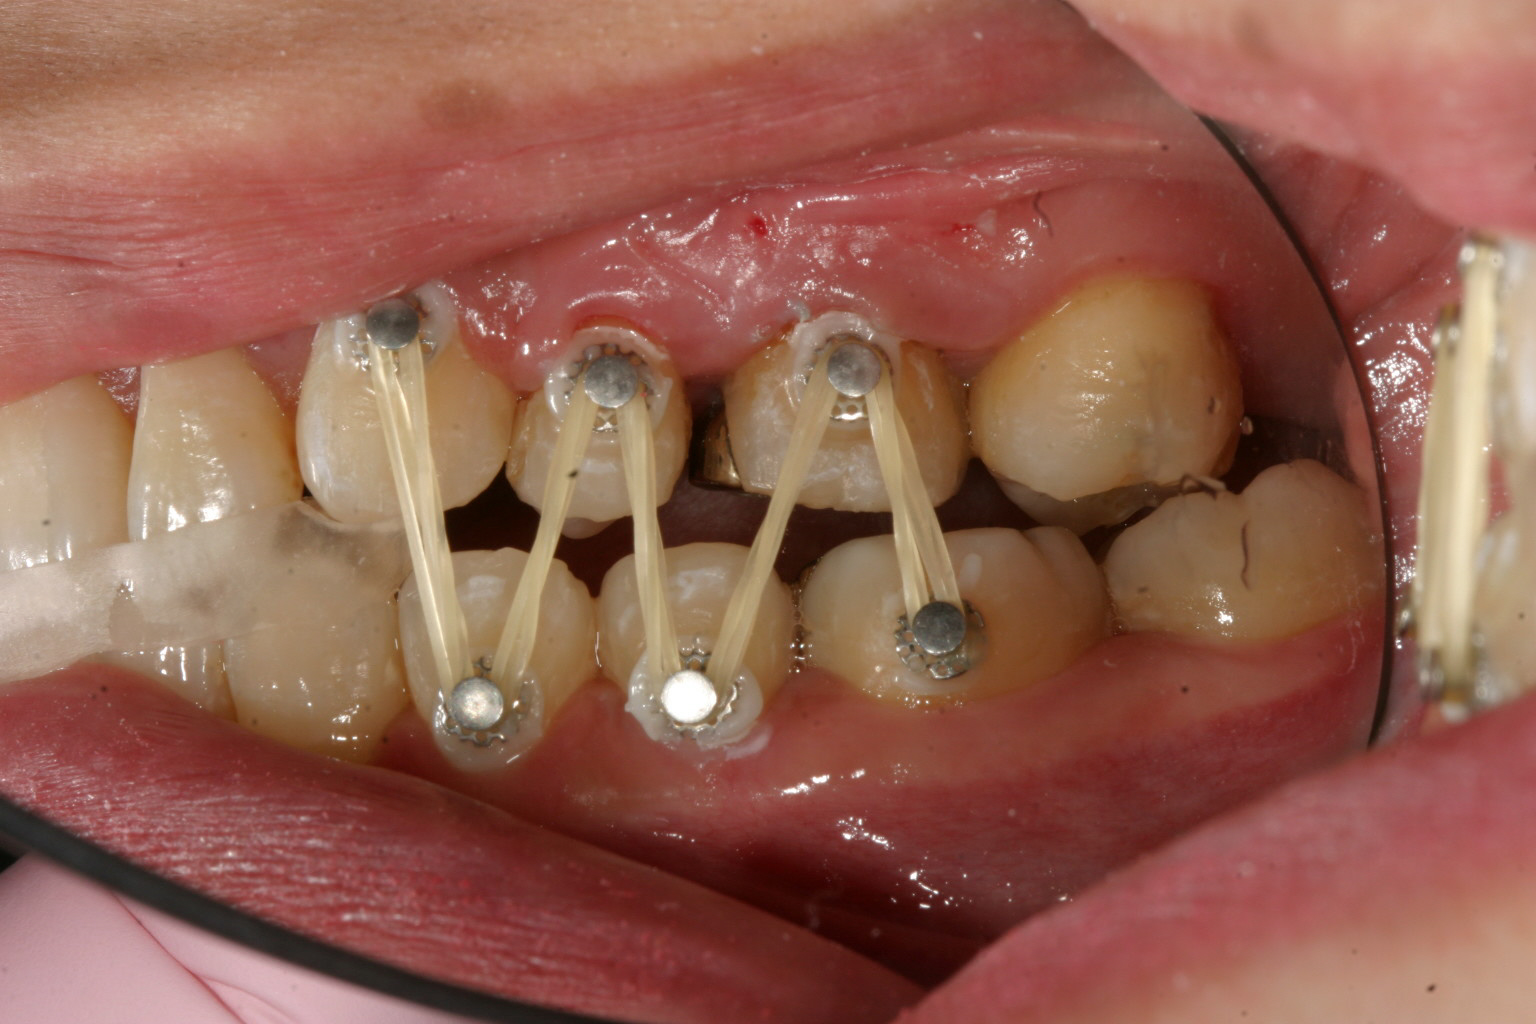

臼歯部離開の為前歯に自家製咬合閉鎖ジグを前歯に咬まして臼歯部にボタン付けてアップダウンエラスティック使用。

今回は出っ歯観改善の為、左側上顎小臼歯を1本だけ抜歯しました。

あとは上顎の歯のねじれ改善、下顎の舌側転移も難なく出っ歯も改善しました。